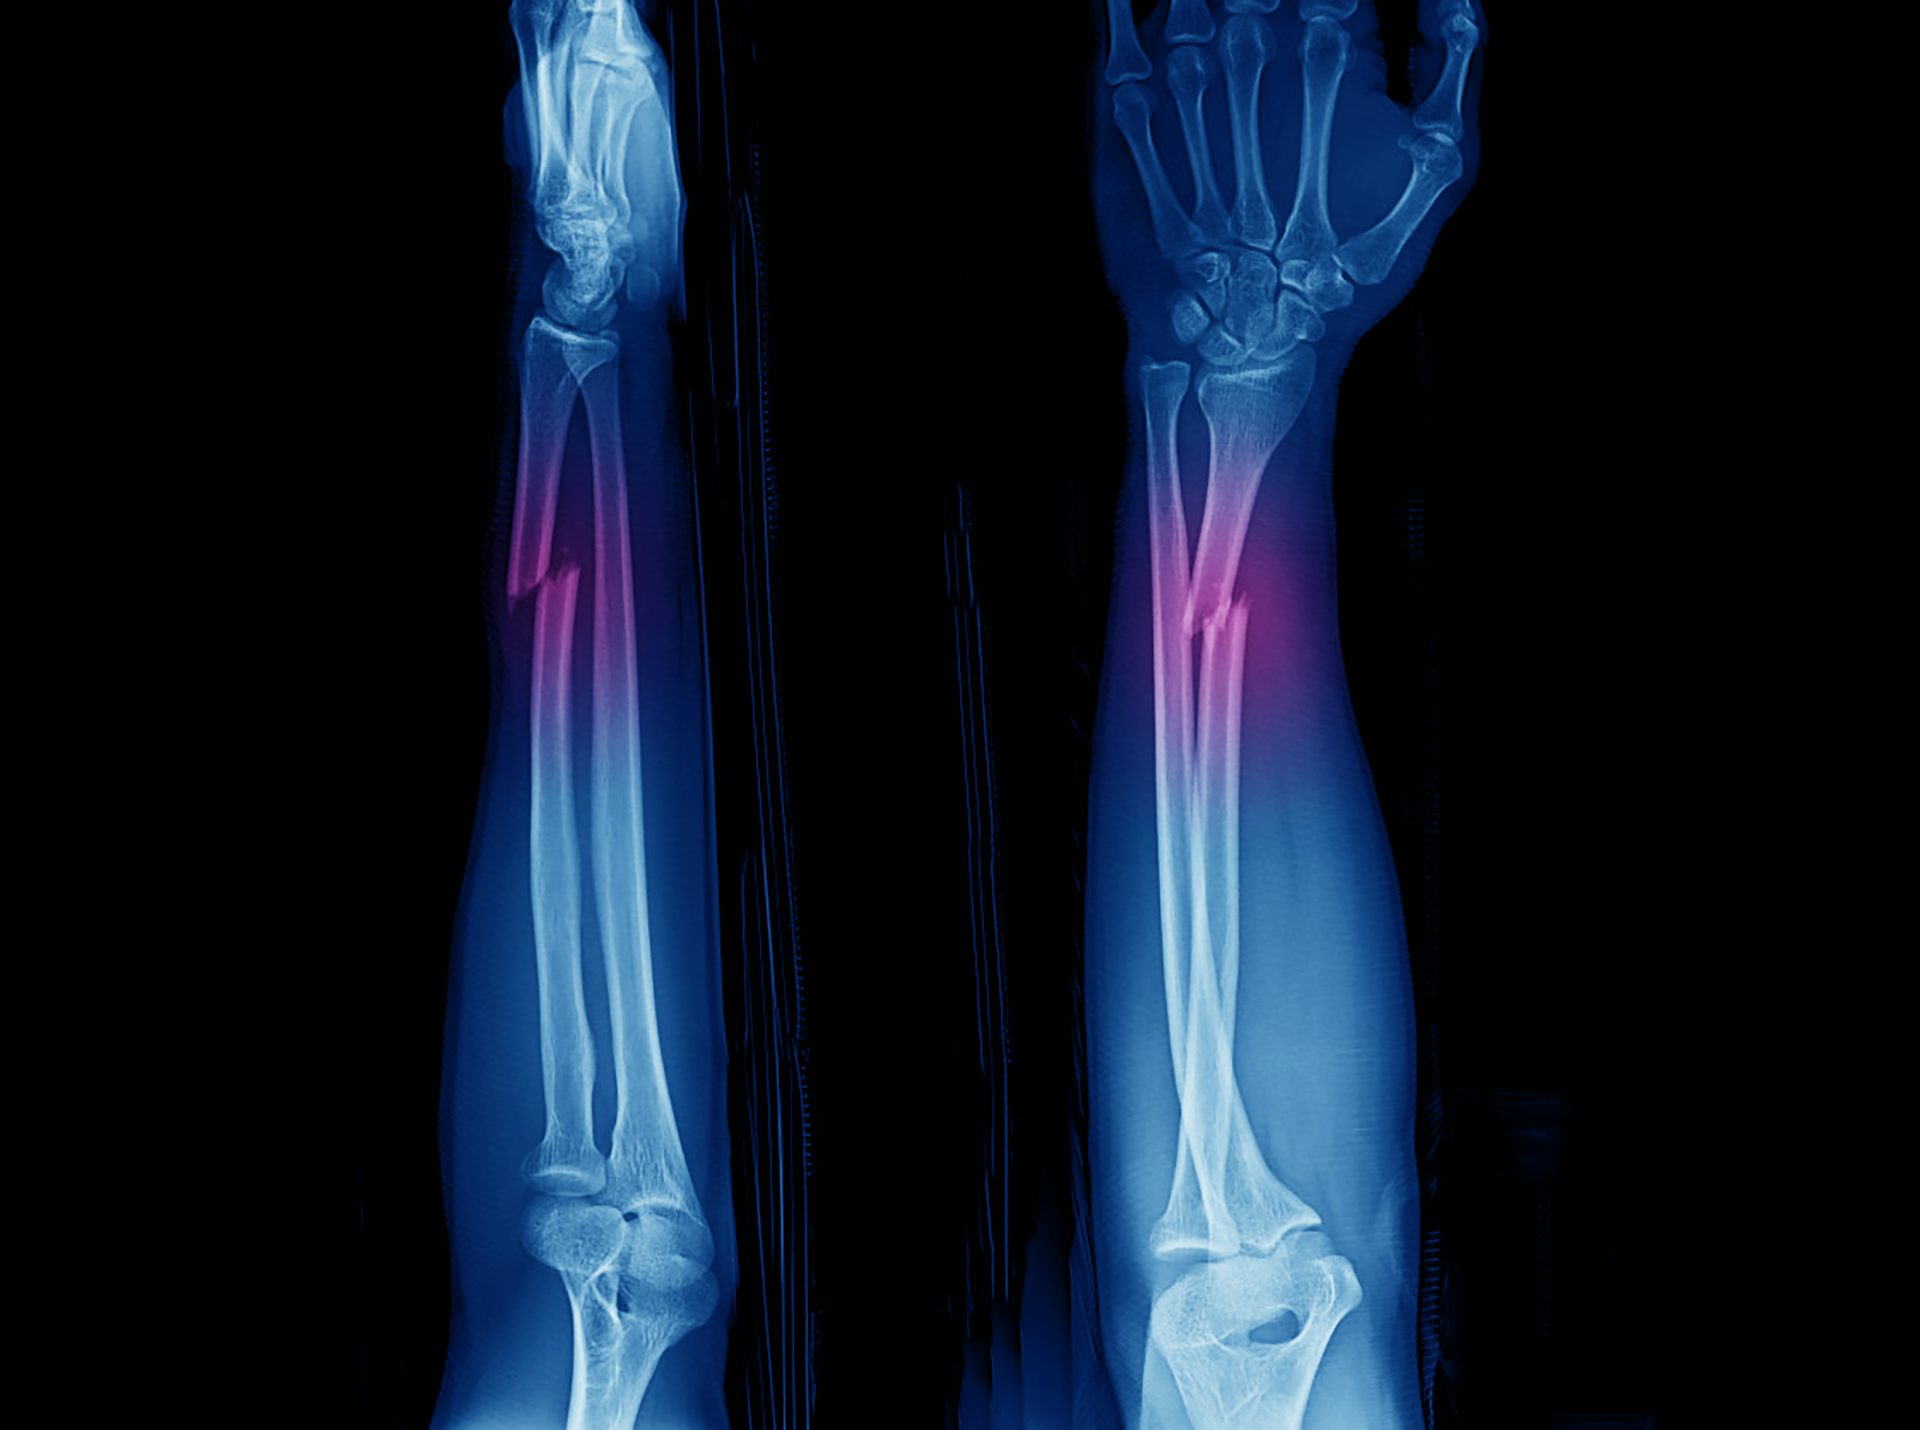

The conversation(L.A.J.cousiño) — Aproximadamente uno de cada 15 000 recién nacidos padece osteogénesis imperfecta, también conocida como la “enfermedad de los huesos cristal”. Esta patología hereditaria se caracteriza por una modificación en la formación del colágeno debido a una alteración genética, lo cual implica que los huesos sean más frágiles y se fracturen con mayor facilidad.

Los afectados pueden experimentar desde manifestaciones leves (deformidad ósea y escasas alteraciones en otros tejidos, lo que ocurre en la mayoría de los casos) a formas muy graves, asociadas incluso a la muerte en la etapa cercana al parto (período perinatal).

Volviendo al caso que nos ocupa, el colágeno constituye el principal componente orgánico de los huesos y es el que se encarga de proporcionarles flexibilidad y elasticidad. De ahí que su alteración propicie las fracturas o deformaciones características de la oseteogénesis imperfecta.

Para tener unos huesos resistentes se necesita, por lo tanto, una cantidad adecuada de materia en el esqueleto: es lo que se denomina densidad mineral ósea, que hace referencia a la cantidad de calcio en los huesos. Aunque, como pone de manifiesto la osteogénesis imperfecta, otros componentes como el colágeno juegan también un papel fundamental. Al mismo tiempo, la forma del hueso y su arquitectura interna son fundamentales para que pueda soportar cargas sin romperse.